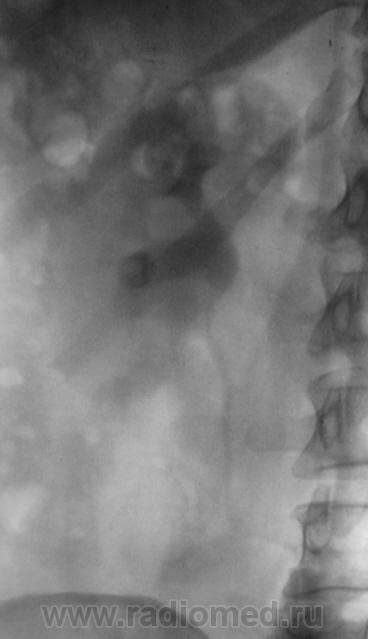

После введения контрастного вещества урограммы произведены на 7 и 15 минутах.

А мне этот конкремент, при всей его "рентгеноположительности", видится дефектом наполнения чашки, контрастированной ещё более "рентгеноположительным" контрастом)).

Ещё более отчетливо это может было бы увидеть на прицельной рентгенограмме почки либо томограмме её.

Данный случай не томографировался.